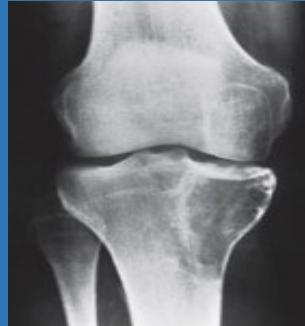

| Look | Compare both limbs, Skin, Muscle bulk, bony landmarks, hair distribution | Assess symmetry, signs of trauma, inflammation, muscle atrophy, structural changes | Visual examples - Skin, Muscle, Bone, Joint: ![]() ![]() ![]() ![]() ![]() ![]() | Swelling, scars, discoloration, hair changes, muscle wasting, bony protrusions, angulation, redness |